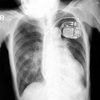

さっそく12誘導心電図です。

https://litfl.com/digoxin-toxicity-ecg-library/

(Ex.1)

*調律は心房調律ですP波がある。

*心室性の二段脈で、PVC多発です。設問にジギタリス中毒があったら、考慮する。但し、ジギタリス投与なしでも起きます。